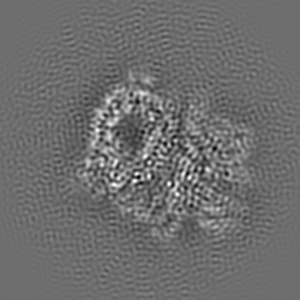

Human Huntingtin-HAP40 complex structure

4.0 Å

Sample: Huntingtin-HAP40 complex

Fitted models: 6ez8

The cryo-electron microscopy structure of huntingtin.

Guo Q , Cheng J, Seefelder M, Engler T , Pfeifer G, Oeckl P, Otto M , Moser F , Maurer M, Pautsch A, Baumeister W, Fernandez-Busnadiego R , Kochanek S

(2018) Nature , 555 , 117 - 120